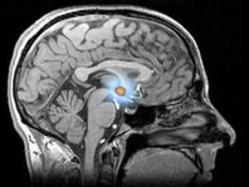

Incluso cuando somos mesurados, y seguimos indicaciones de un doctor, el uso de sustancias químicas genera efectos secundarios en el organismo, los cuales pueden ser controlados si se actúa bajo prescripción médica. Sin embargo, si se trata de un caso de “mal uso” en el que la dependencia a la sustancia nos lleva a reincidir, el organismo experimentará un deterioro gradual, y adicional a esto la salud mental, y estabilidad emocional para afrontar situaciones se verán seriamente alteradas. Por otra parte el desarrollo social y adaptación de quien las consume se dificulta debido a los trastornos de personalidad generados por la alteración y deterioro de estructuras y procesos neurológicos.

Incluso cuando somos mesurados, y seguimos indicaciones de un doctor, el uso de sustancias químicas genera efectos secundarios en el organismo, los cuales pueden ser controlados si se actúa bajo prescripción médica. Sin embargo, si se trata de un caso de “mal uso” en el que la dependencia a la sustancia nos lleva a reincidir, el organismo experimentará un deterioro gradual, y adicional a esto la salud mental, y estabilidad emocional para afrontar situaciones se verán seriamente alteradas. Por otra parte el desarrollo social y adaptación de quien las consume se dificulta debido a los trastornos de personalidad generados por la alteración y deterioro de estructuras y procesos neurológicos.

Incluso cuando somos mesurados, y seguimos indicaciones de un doctor, el uso de sustancias químicas genera efectos secundarios en el organismo, los cuales pueden ser controlados si se actúa bajo prescripción médica. Sin embargo, si se trata de un caso de “mal uso” en el que la dependencia a la sustancia nos lleva a reincidir, el organismo experimentará un deterioro gradual, y adicional a esto la salud mental, y estabilidad emocional para afrontar situaciones se verán seriamente alteradas. Por otra parte el desarrollo social y adaptación de quien las consume se dificulta debido a los trastornos de personalidad generados por la alteración y deterioro de estructuras y procesos neurológicos.